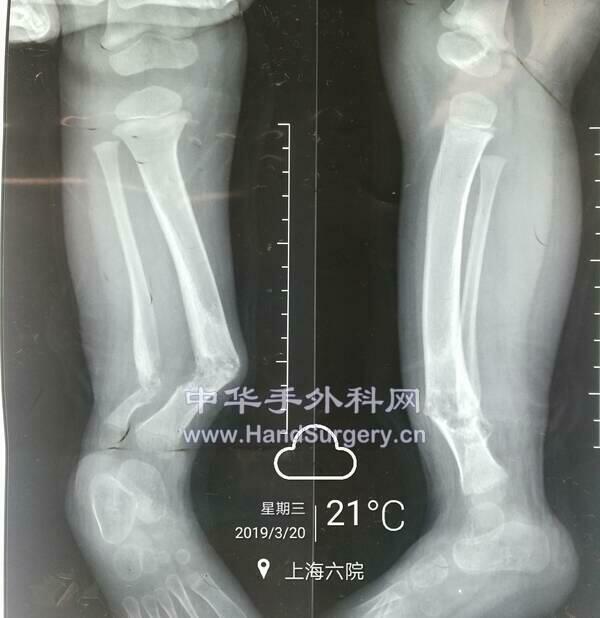

佝偻病截骨矫形手术

IMG_20190320_135858.jpg